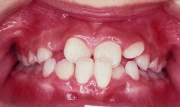

早期治療

早期治療後